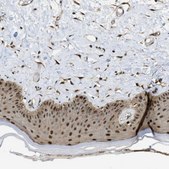

IF, IHC

immunoblotting: 0.04-0.4 μg/mL, immunofluorescence: 0.25-2 μg/mL, immunohistochemistry: 1:200-1:500

All Prestige Antibodies Powered by Atlas Antibodies are developed and validated by the Human Protein Atlas (HPA) project and as a result, are supported by the most extensive characterization in the industry.

The Human Protein Atlas project can be subdivided into three efforts: Human Tissue Atlas, Cancer Atlas, and Human Cell Atlas. The antibodies that have been generated in support of the Tissue and Cancer Atlas projects have been tested by immunohistochemistry against hundreds of normal and disease tissues and through the recent efforts of the Human Cell Atlas project, many have been characterized by immunofluorescence to map the human proteome not only at the tissue level but now at the subcellular level. These images and the collection of this vast data set can be viewed on the Human Protein Atlas (HPA) site by clicking on the Image Gallery link. We also provide Prestige Antibodies® protocols and other useful information.

• IHC tissue array of 44 normal human tissues and 20 of the most common cancer type tissues.